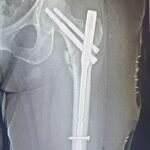

Trauma surgery involves the treatment of fractures and injuries caused by accidents, falls, or high-impact injuries. These injuries may affect bones, joints, and surrounding soft tissues, and often require timely surgical intervention to restore alignment, stability, and function.

Complex trauma surgery is required for severe injuries such as multiple fractures, joint injuries, open fractures, or injuries involving previous implants or deformities. These cases need advanced surgical techniques, careful planning, and specialized orthopedic expertise. The aim of trauma and complex trauma surgery is to promote proper healing, restore movement, and help patients return to daily activities safely.